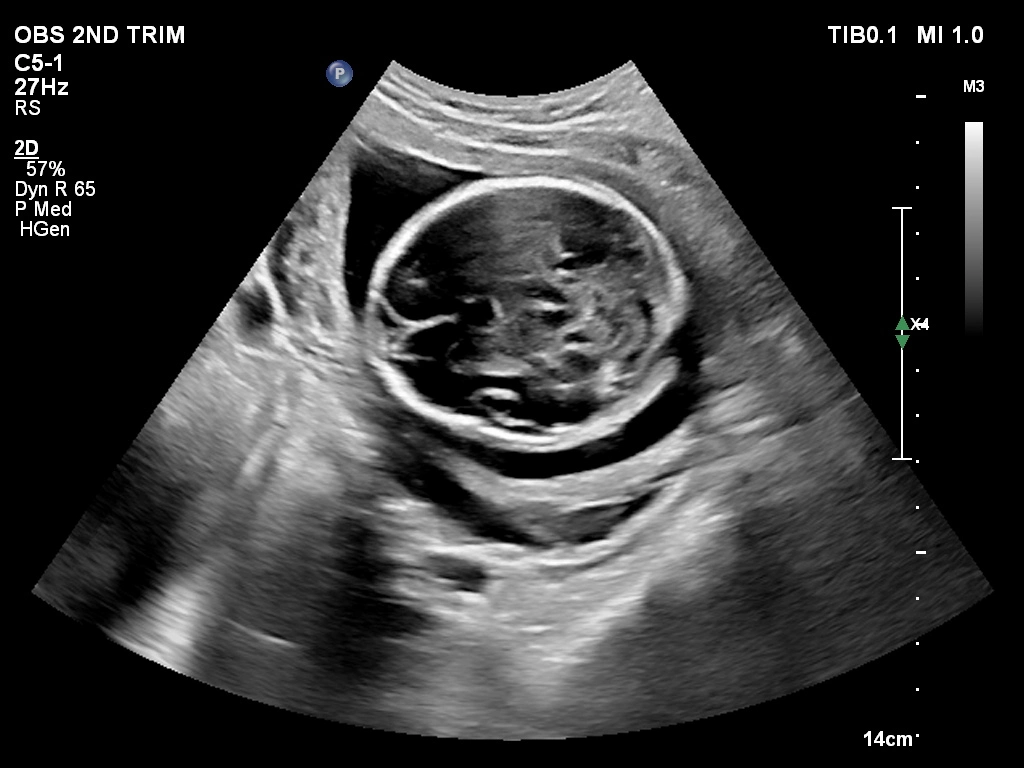

🔹 Anomaly Scan (Level II Ultrasound)

Anomaly Scan is a detailed ultrasound performed during pregnancy (usually between 18 and 22 weeks) to check the baby’s development. It helps detect structural abnormalities in the brain, heart, spine, kidneys, and other organs. This scan ensures your baby is growing normally and helps doctors identify any potential complications early. If you are looking for a reliable anomaly scan in Kathmandu, an early and accurate diagnosis is essential for a safe pregnancy.